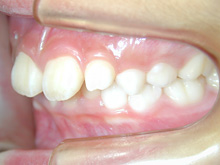

新舞子在住 I.Y様(15歳女性)

患者様は上下顎歯列弓の狭窄と上下顎前歯の叢生を主訴としてお母様とともに来院されました。

近隣のかかりつけの歯科医院で小児の頃より将来的な矯正治療の必要性をお話しいただいたそうです。

そのころからの将来矯正歯科治療の場合には抜歯の必要がある可能性も指摘されたともお話があったそうです。

お母様は初診時に当院での矯正歯科治療をご希望されていたので速やかに診断を行うよう

基本的な口腔内検査、口腔内・正貌、側貌写真撮影、レントゲン撮影、模型採得しました。

犬歯関係・臼歯関係は良好です。

![]() |

犬歯関係・臼歯関係は良好ですので、かみ合わせを崩さないように矯正治療をすすめます。

上下顎前歯の叢生を改善するために上下顎両側第1小臼歯を4歯抜歯して治療します。

0.14インチラウンドのニッケルチタンワイヤーで治療開始して0.16×0.16レクタンワイヤーで治療をすすめていき叢生を改善します。

できたスペースを利用して叢生の改善と臼歯のかみ合わせの改善を行います。

治療の前に叢生のためずれていた中切歯の正中は一致しています。犬歯関係、臼歯関係も1対2歯でよく咬んでいます。

口腔衛生状態が治療中に不良でした。

装置がとれ、歯列が改善されたので口腔衛生状態の改善を期待してブラッシング等のオーラルセルフケアに重要性を説明しました。

後戻りを防ぐには保定が重要でリテーナーの使用を強く指導しました。

治療費用:60万円

動的治療期間:2年4か月